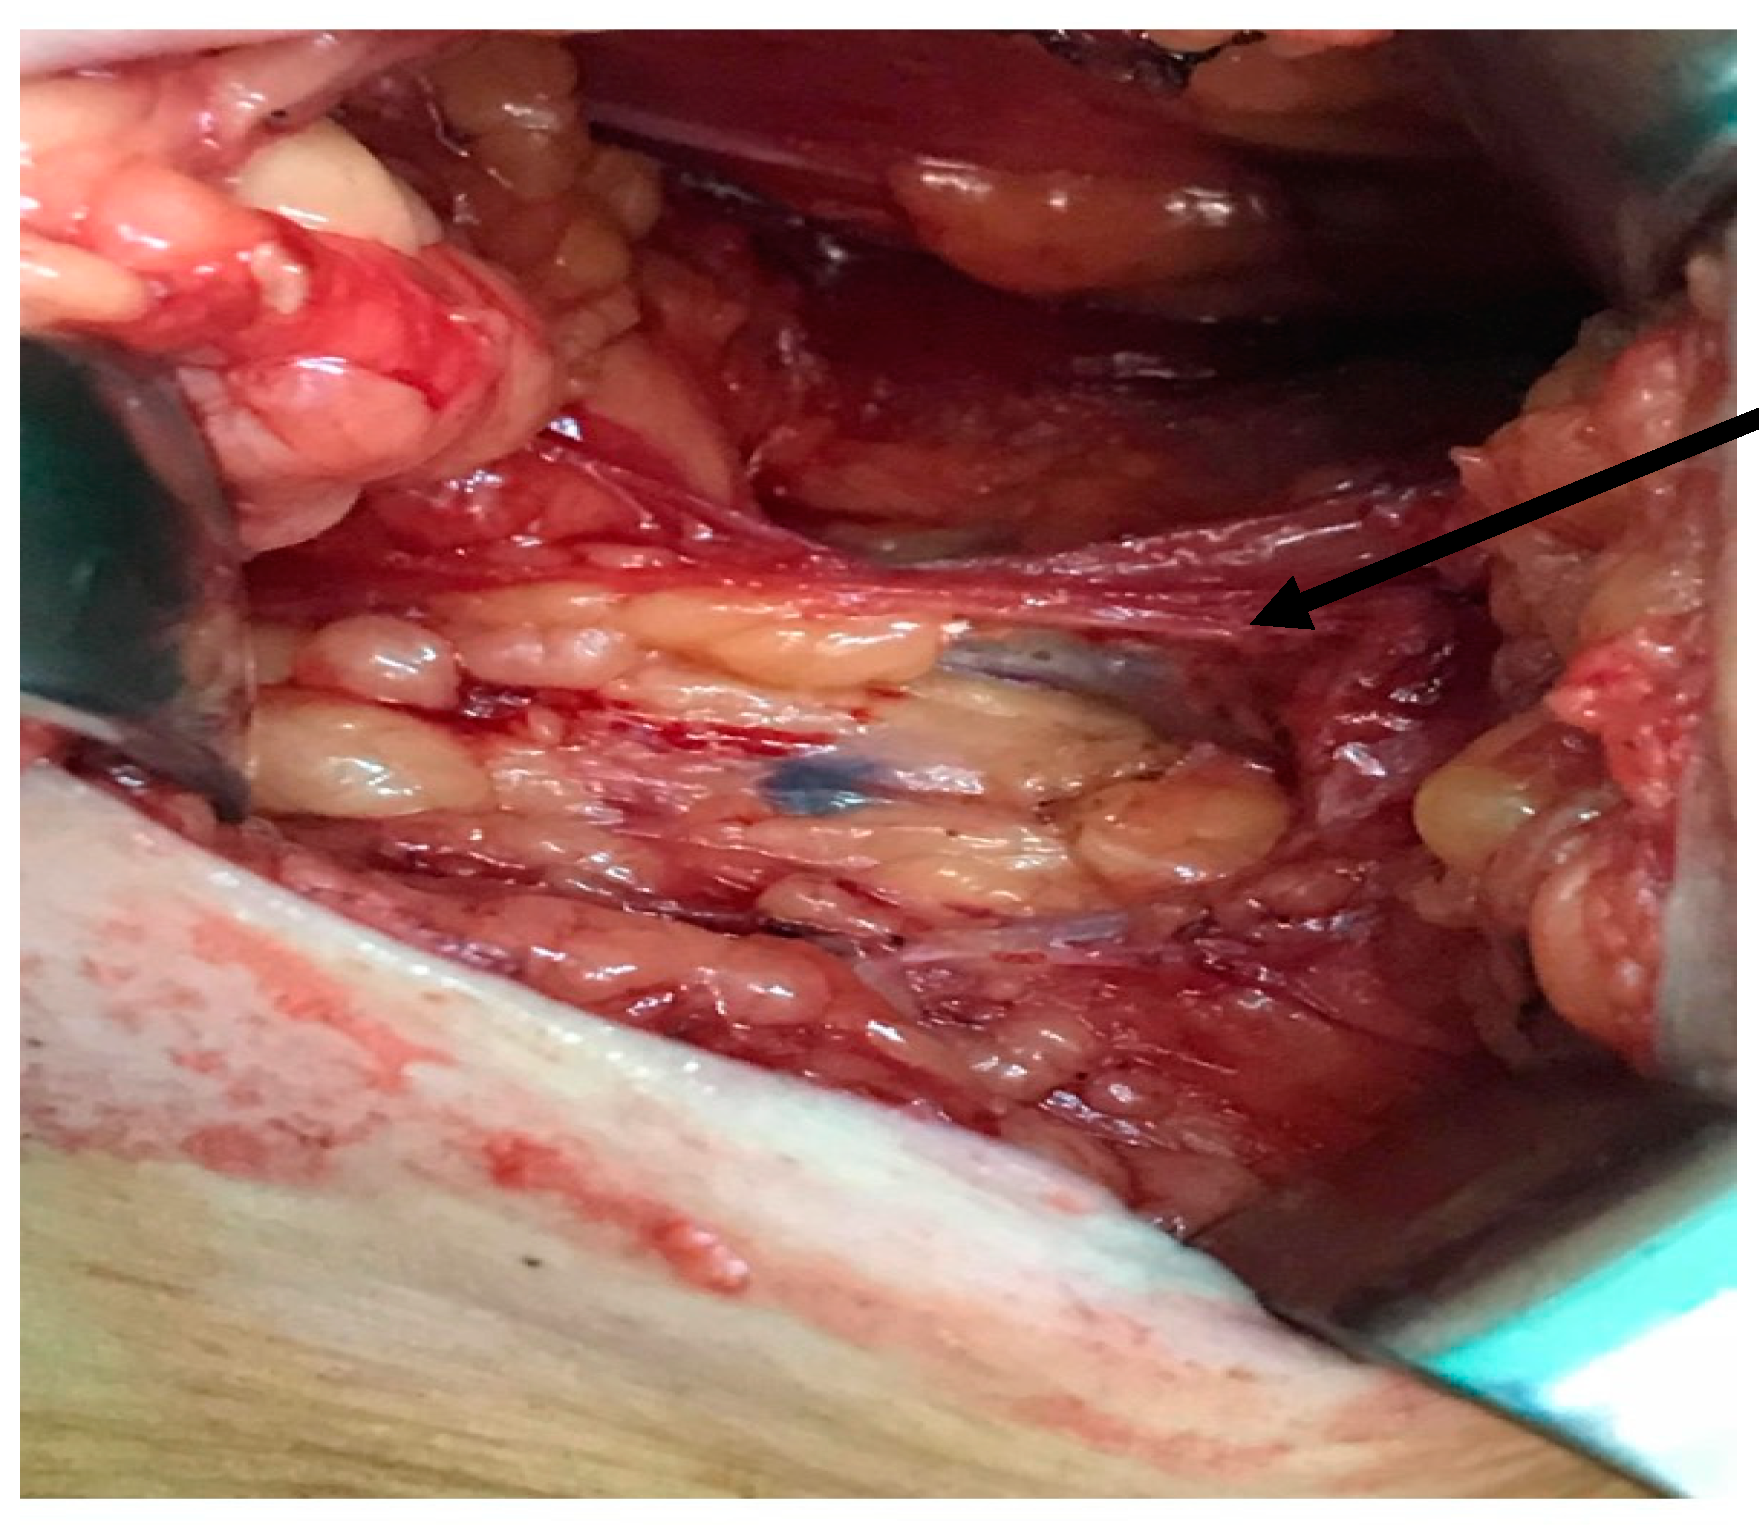

2.2. Surgical Technique